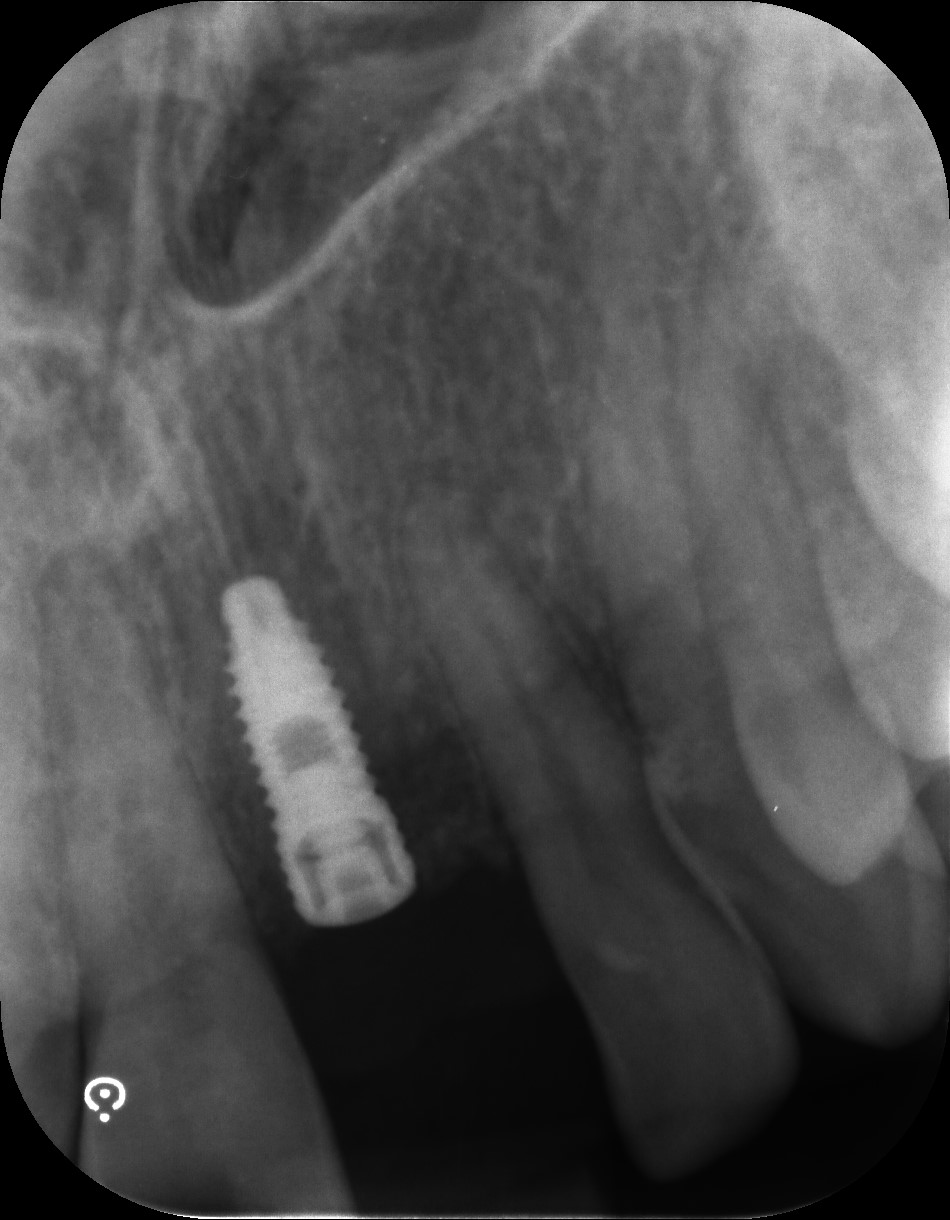

Examples of our work.

Single front tooth case